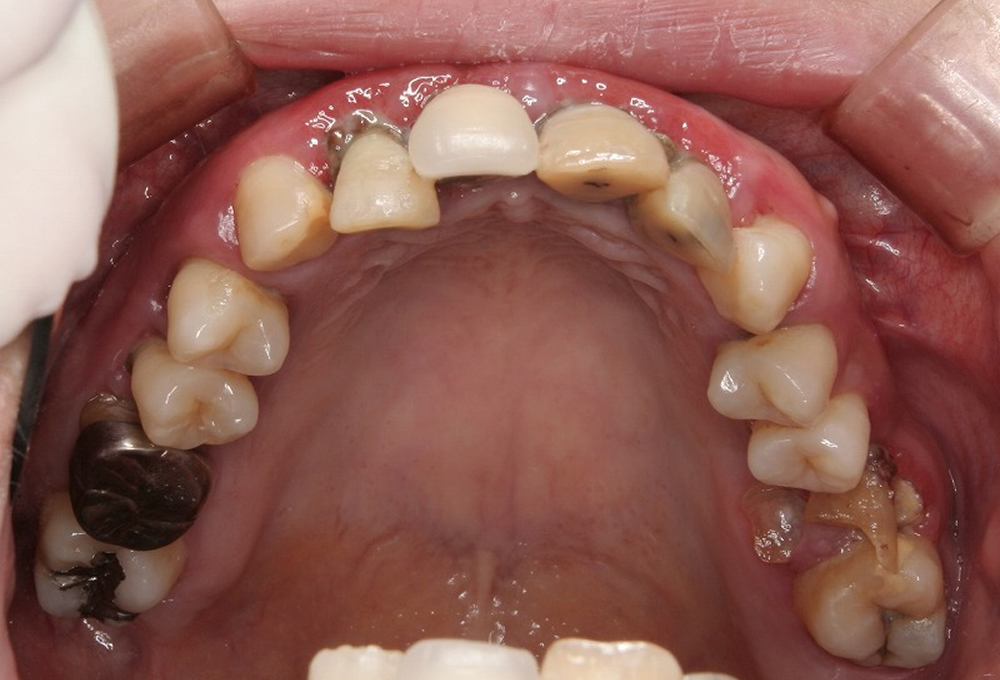

②術前 上顎